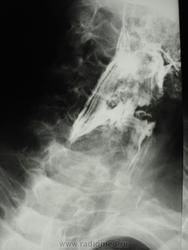

мужчина 1932 г.р. (лежачий пациент, инвалид) привезли со скорой на рентфию ОГК. случайно оказалась рядом и выяснила у сына, что он 3 дня не разговаривает и не кушает. Решила дать глоток бария пока лежит(снимки наспине), вот что получилось....

Образование или инородное тело?

С учетом таких контуров образования возможно лейомиома, но расположение странное, а может образование идет со стороны щитовидной железы?

наверно инородное тело врядли (большое какое то), может из щитовидки что то прорасло??? а может вообще заглоточный абсцесс????

Ну, у стариков инородное тело (кусок мяса) может дать интересные картинки.

Уж больно четкий кусочек мяса, с учетом если с зубами не все в порядке.

Тоже на все 100% соглашаюсь с Валентином Львовичем, в первую очередь необходимо исключать т.н. "мясной завал", а мясо там...сало ...или еще что - дело десятое.....